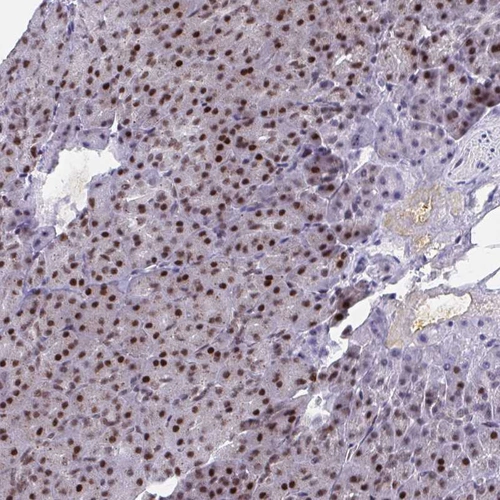

Immunohistochemistry analysis in human testis and skeletal muscle tissues using HPA059621 antibody. Corresponding YTHDF2 RNA-seq data are presented for the same tissues.